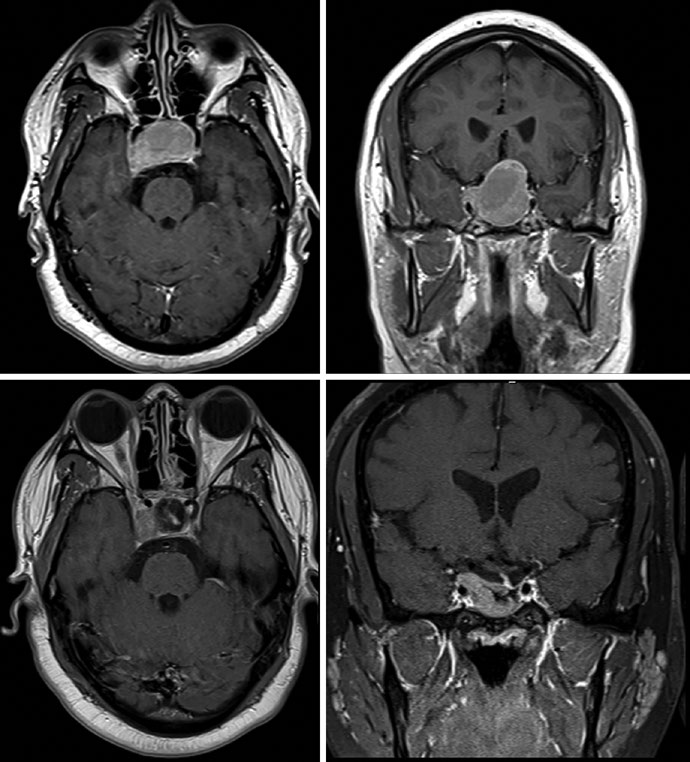

El caso de la Figura 29.9 ilustra un schwannoma vestibular derecho en el ángulo cerebelopontino que comprime el pedúnculo cerebeloso medio y el puente, extendiéndose hasta el fondo del canal auditivo interno. Existe compresión del tronco encefálico y del nervio trigémino cisternal, con borramiento parcial moderado del cuarto ventrículo. En la Figura 29.10, el tratamiento de un schwannoma del APC izquierdo con SRS a 12,5 Gy de prescripción muestra la isodosis de prescripción cubriendo el tumor, con isodosis de 20 Gy en el centro y 5 Gy en la periferia, preservando tronco encefálico y cóclea como OARs.